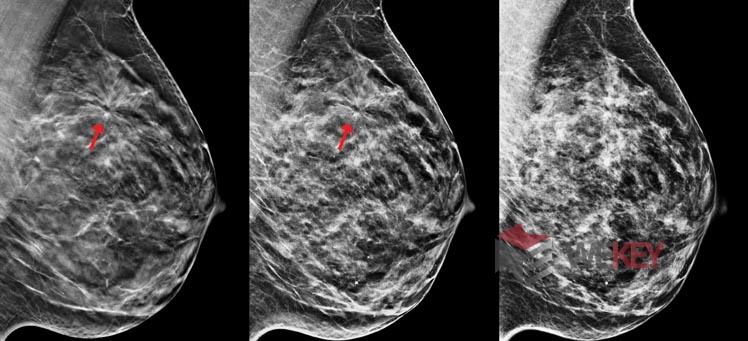

Чтобы проверить свою гипотезу, исследователи провели два эксперимента: в первом участникам предлагалось попробовать себя в роли оператора досмотра в аэропорту, а во втором – врача-маммолога.

Во втором эксперименте приняли участие 18 человек, которым было объяснено, как идентифицировать опухоль на маммограмме. Затем им продемонстрировали 400 уникальных снимков, 5% из которых имели опухоль, а затем еще 400, из которых опухоль имели 50%. В обоих случаях наблюдалось значительное увеличение частоты обнаружения при объединении результатов двух участников.

Задачи интроскопа в аэропорту и рентгена в больнице не так уж и различны. Задача заключается в том, что вам нужно найти то, что в жизни приходится видеть не часто. «Неважно, ищете ли вы опухоль, оружие или что-то еще, объединение двух разных суждений об одном и том же просмотренном снимке значительно улучшает показатели обнаружения», - резюмируют исследователи.